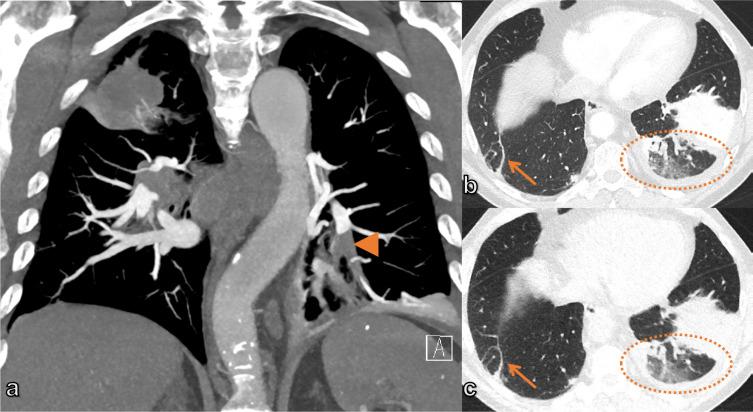

Imaging in patients with acute dyspnea when cardiac or pulmonary origin is suspected.

A wide spectrum of conditions, from life-threatening to non-urgent, can manifest with acute dyspnea, thus presenting major challenges for the treating physician when establishing the diagnosis and severity of the underlying disease. Imaging plays a decisive role in the assessment of acute dyspnea of cardiac and/or pulmonary origin. This article presents an overview of the current imaging modalities used to narrow the differential diagnosis in the assessment of acute dyspnea of cardiac or pulmonary origin. The current indications, findings, accuracy, and limits of each imaging modality are reported. Chest radiography is usually the primary imaging modality applied. There is a low radiation dose associated with this method, and it can assess the presence of fluid in the lung or pleura, consolidations, hyperinflation, pneumothorax, as well as heart enlargement. However, its low sensitivity limits the ability of the chest radiograph to accurately identify the causes of acute dyspnea. CT provides more detailed imaging of the cardiorespiratory system, and therefore, better sensitivity and specificity results, but it is accompanied by higher radiation exposure. Ultrasonography has the advantage of using no radiation, and is fast and feasible as a bedside test and appropriate for the assessment of unstable patients. However, patient-specific factors, such as body habitus, may limit its image quality and interpretability. Advances in knowledge This review provides guidance to the appropriate choice of imaging modalities in the diagnosis of patients with dyspnea of cardiac or pulmonary origin.